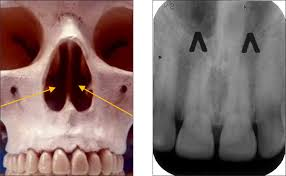

incisive foramen

anterior hard palate at midline

incisive canal

opening via incisive foramen